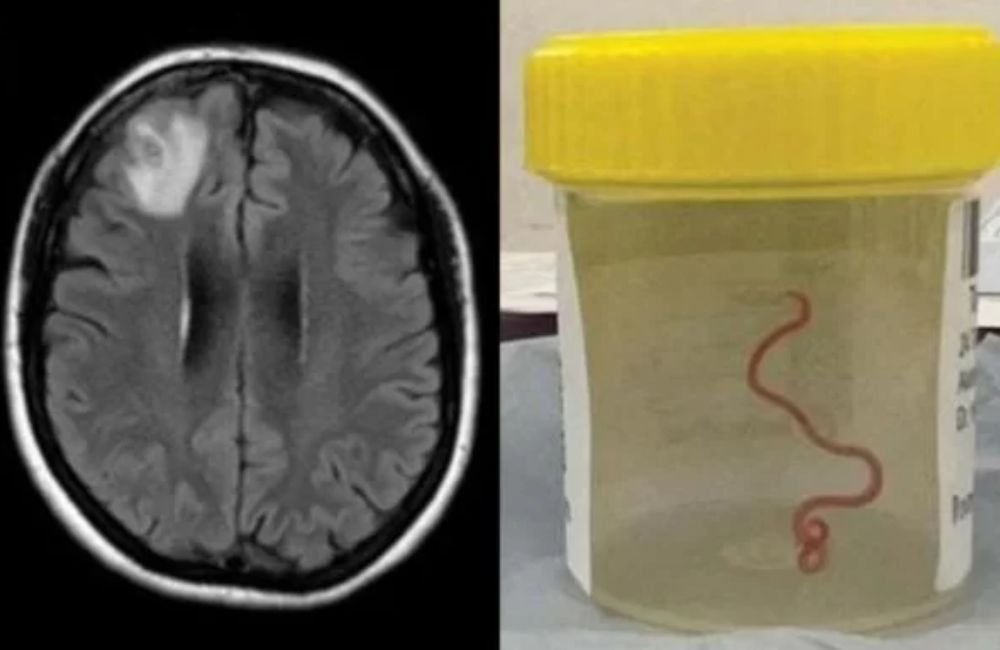

Verme de 8 cm é encontrado em cérebro humano pela primeira vez